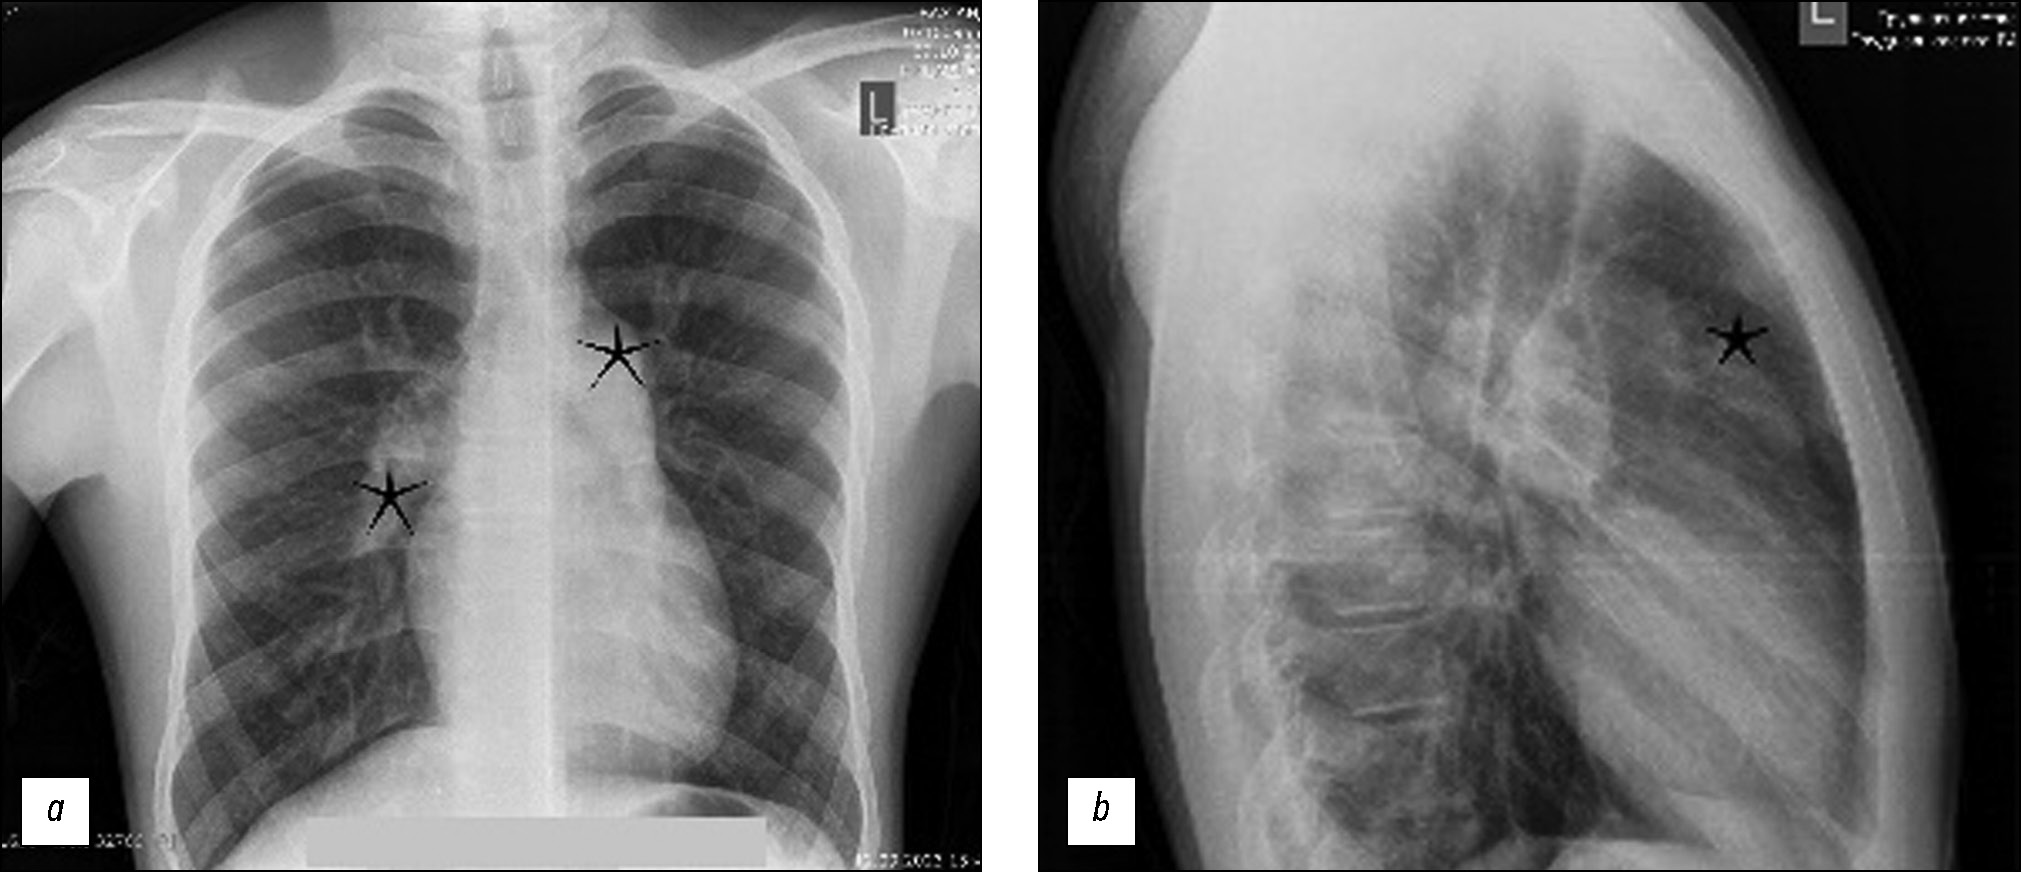

通过计算机断层扫描血管造影发现年轻肺动脉高压患者的肺动脉假性动脉瘤

摘要

假性动脉瘤和肺动脉瘤是一种罕见的疾病,但与之相关的并发症强调了识别它们的重要性。本文介绍了一名15岁患者的临床病例,该患者因咯血而入院。经诊断,发现左肺动脉瘤。随后的计算机断层扫描血管造影和肺动脉介入治疗结果证实存在肺动脉瘤,这表明咯血是由于动脉瘤破裂造成的。肺动脉介入证实了确诊。肺动脉瘤的早期发现和治疗至关重要,尤其是对年轻患者,因为及时干预可以预防严重并发症,改善疾病预后。提高对这些血管疾病的认识,并通过相应的诊断措施和干预措施对其进行及时处理,可以帮助医疗服务者有效降低与肺动脉瘤相关的潜在风险,从而提高预后准确性和医疗服务质量。